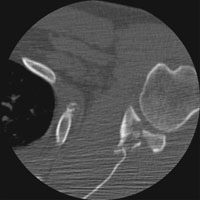

- Click on the image for a larger versionAAxial CT. This image through the glenoid shows a comminuted intraarticular fracture.